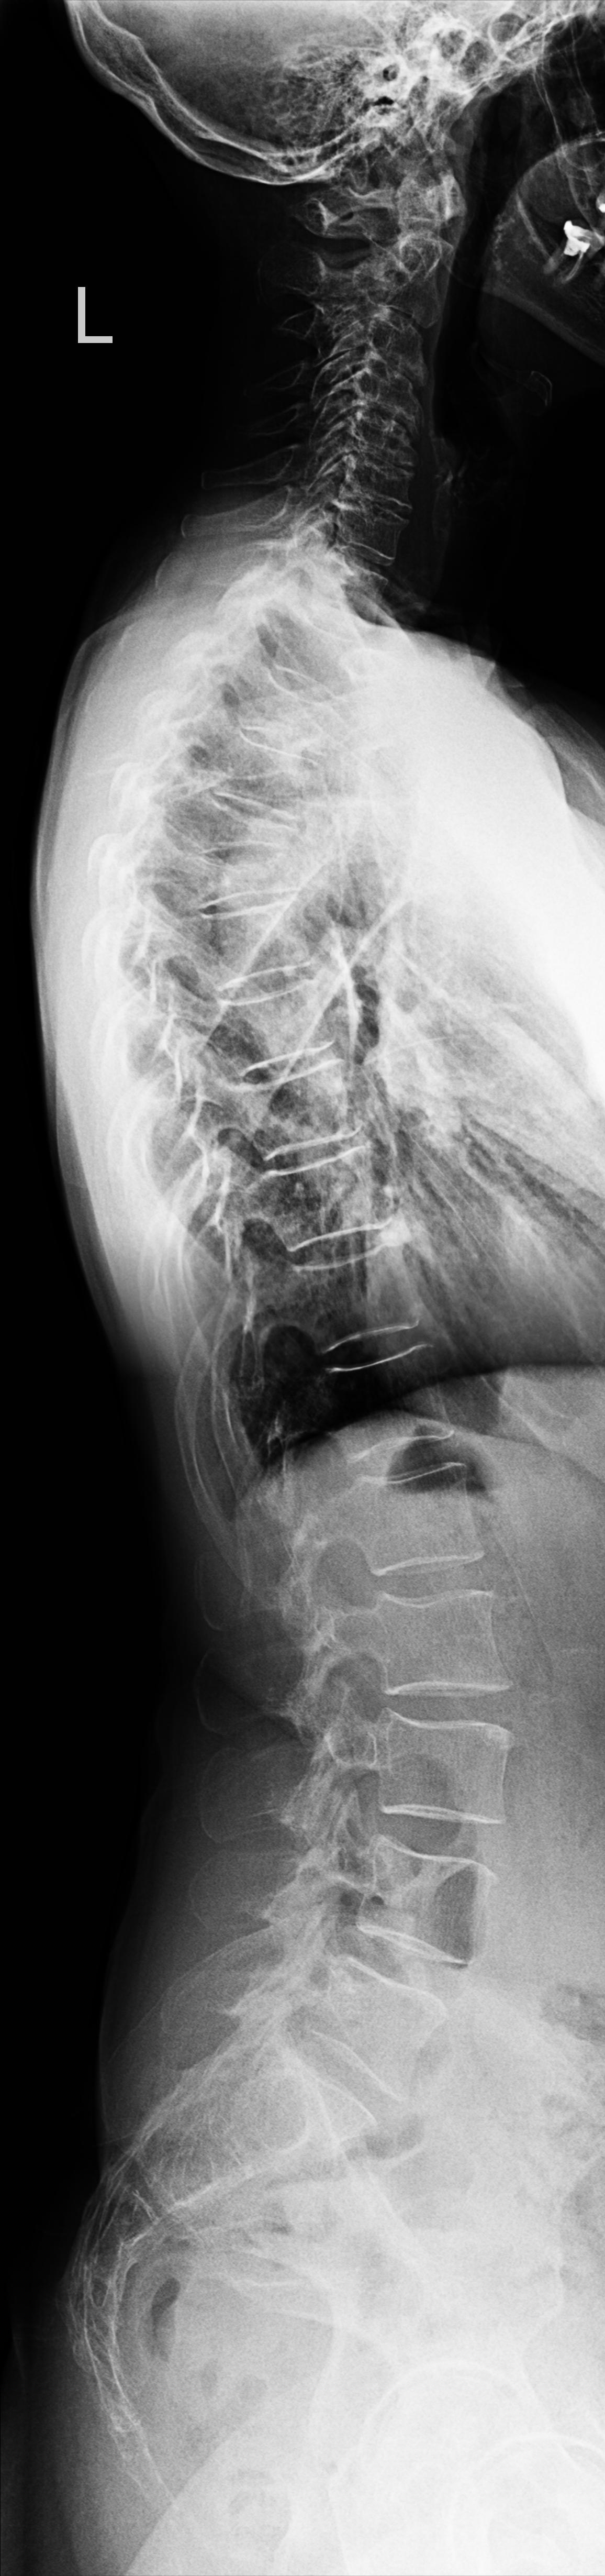

Wirbelsäule Ganzaufnahme lateral

Es wurden keine Bilder gefunden.

Technik

• FDA: 3 m

• Ausgangsformat: 3 x 35/43

Indikation

Beurteilung der Wirbelsäulestatik, Kyphose und Skoliose.

Lagerung

Mit der Seite am Rasterwandstativ

Kopf in Neutralstellung

Arme nach vorne ausstrecken

Händen kreuzen damit die Schulterblätter rausgezogen werden

Zentralstrahl

Senkrecht auf Wirbelsäule

Einblendung

von Oberlippe bis einschließlich Hüftköpfe

Qualitätskriterien

HWS-BWS-LWS mit Sakrum sollte vollständig und gut beurteilbar abgebildet sein.

Anmerkung

Spezialstativ mit Raster oder Digitalaufnahme mit Abbildung eines Rasters zur Vermessung. Evtl Ausgleichschuhe ausziehen und auch ggf. Verlaufsfilter für guten Kontrast verwenden.